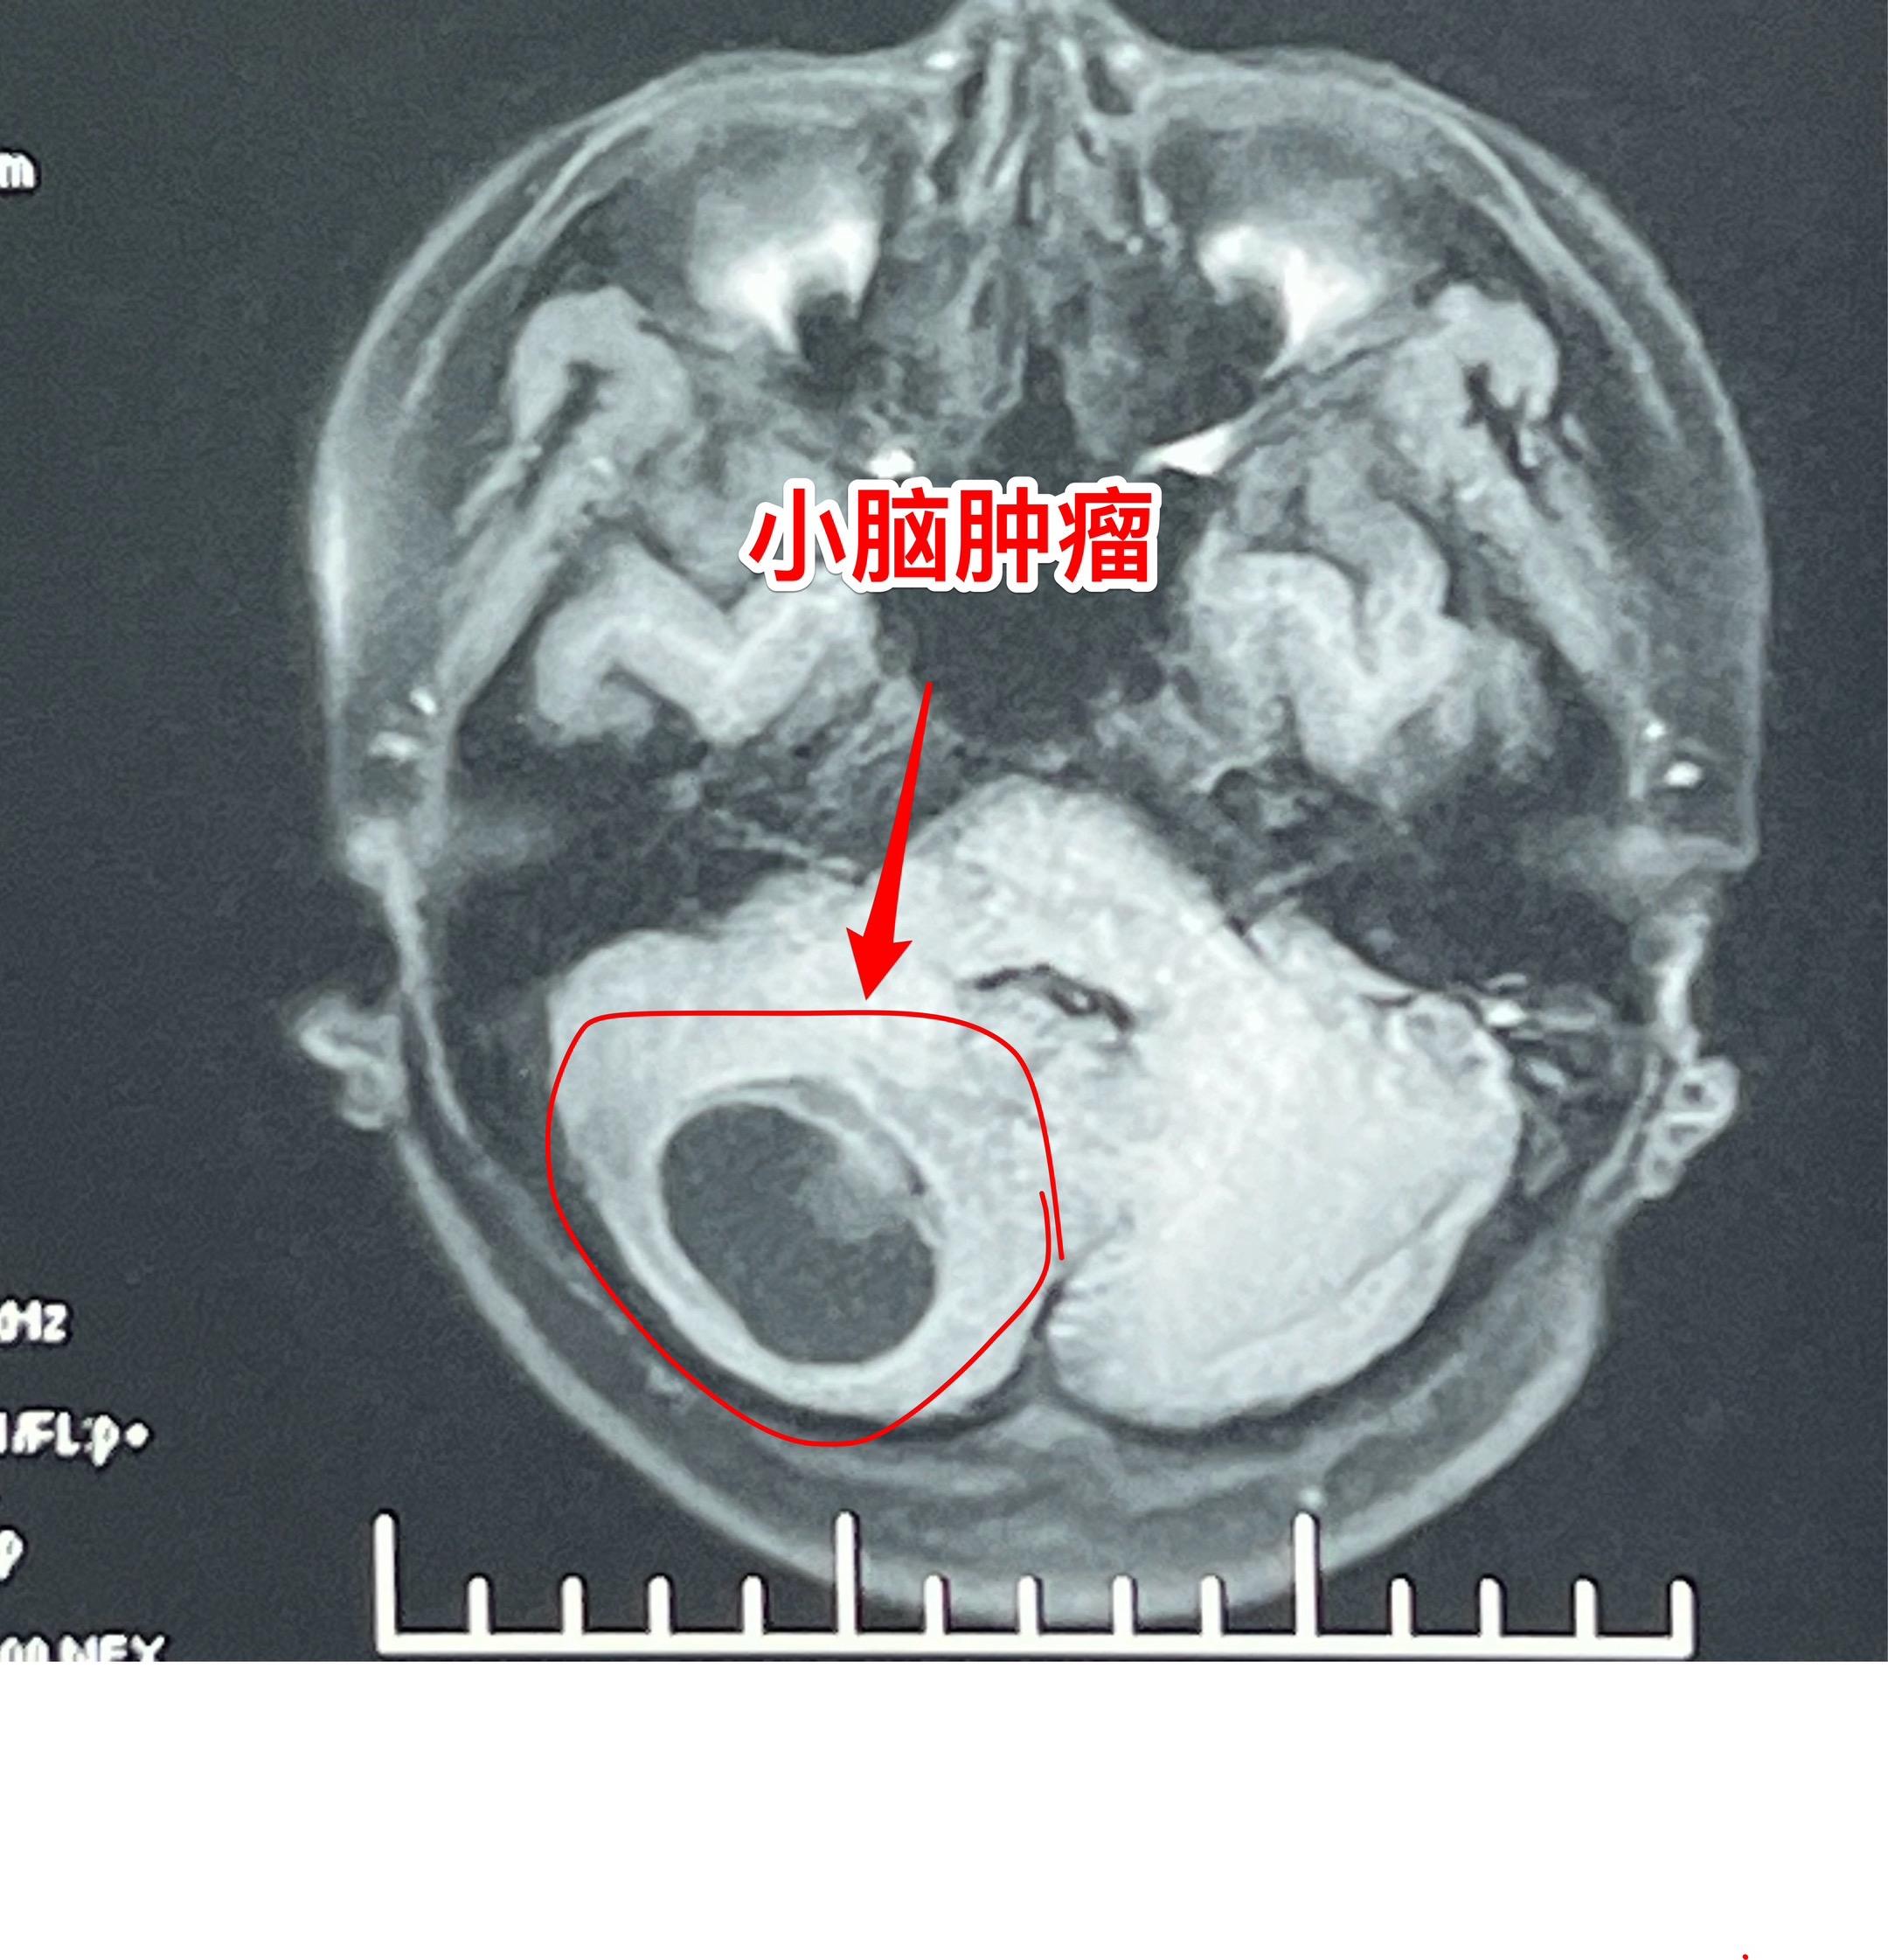

小孩子脑肿瘤中最常见的是小脑肿瘤。与大人相比,小孩子一般是不容易患上肿瘤性疾病的。然而,小孩子也会患上肿瘤性疾病,其中包括脑部肿瘤、白血病、骨肿瘤等等。 小孩子的脑肿瘤中最常见的小脑肿瘤,小脑肿瘤经常导致病人呕吐。所以,小孩子在没有感冒症状的前提下出现反复呕吐症状,要想到脑部是不是出了问题? 这个14岁沧州女生平常身体很健康,近5天感觉头晕、恶心、呕吐,在当地医院就医,行脑部磁共振、CT检查发现了小脑肿瘤。用甘露醇降颅压后她的症状明显减轻了。6月27日下午到我科来住院,6月2